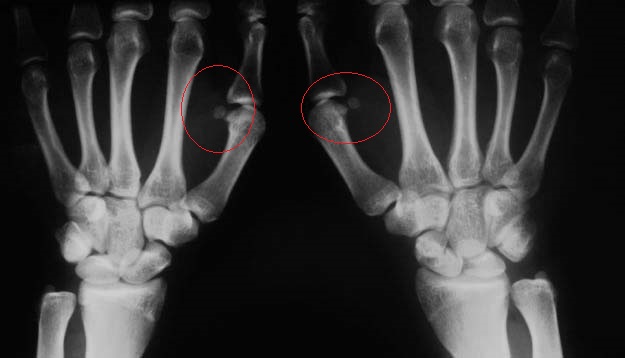

Это добавочная или сесамовидная кость.Таких у нас в организме много.

Мало того, появление этих костей у подростков является признаком полового созревания.

сесамовидные кости у І пястнофалангового сочленеия появляются в период полового созревания к 12 - 14 годам (у девочек чаще к 12, у ребят - позже). http://www.zhuravlev.info/modules.php?op=modload&name=Forum&file=viewtopic&topic=761&forum=6

Да ну, причем тут шутка: Началу активного функционирования половых желез соответствует появление сесамовидной кости в I пястно-фаланговом суставе http://www.medkursor.ru/seksualnoe_zdorove/violation/maturity/4824.html